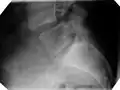

![]() | |

| X-ray of the lateral lumbar spine with a grade III anterolisthesis at the L5-S1 level | |